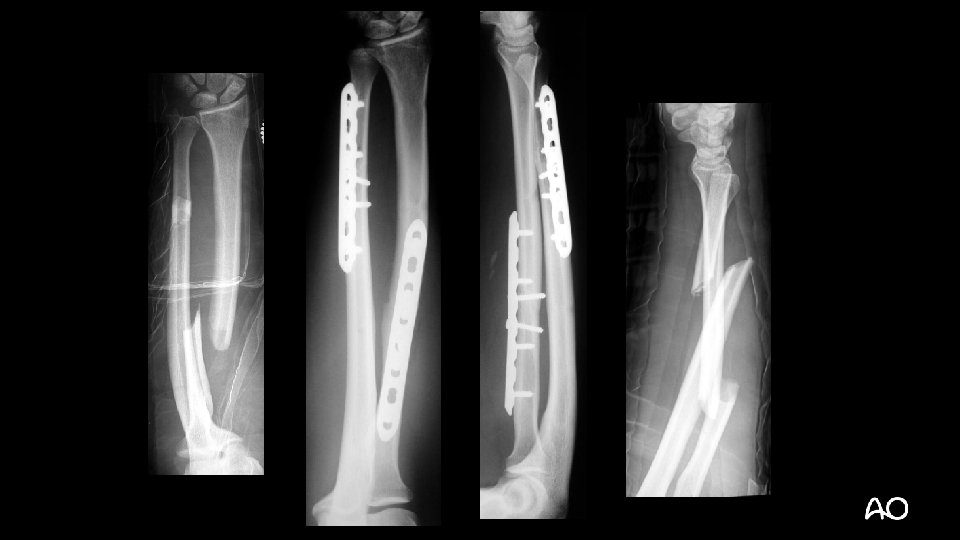

• 32 -year-old man • Motorcycle accident • Isolated injury • Open

2 R 2 B 2 2 U 2 B 2

• 32 -year-old man • How would you expect these fractures to heal?

6 months Absolute stability = direct healing without callus Bridge plate = Relative stability = indirect healing with callus

Summary and take-home message • Forearm fractures, because of their low tolerance for any deformity, should be treated with the principles of articular fractures. • Preoperative planning is essential for better patient outcomes. • The importance of restoration of the anatomical limb axis is stressed. • The fracture configuration will usually determine the type of stability attainable and the type of implant to be used. Module 3, case 4 (slide 8 of 8)